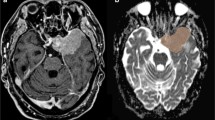

MR images of 70 patients treated with Gamma Knife SRS for WHO grade I meningiomas were retrospectively reviewed. MR acquisition included pre- and post-treatment DWI and DTI sequences, and subtractions were calculated to assess for radiation-induced changes in the parameter values.

After a mean follow-up period (FUP) of 52.7 months, 69 of 70 meningiomas were controlled, with a mean volume reduction of 34.9%. Whereas fractional anisotropy (FA) values of the initial exam showed the highest correlation to tumor volume change at the last FU (CC = − 0.607), followed by the differences between first and second FU values of FA (CC = − 0.404) and the first longitudinal diffusivity (LD) value (CC = − 0.375), the correlation coefficients of all ADC values were comparably low. Nevertheless, all these correlations, except for ADC measured at the first follow-up, reached significance.

For the first time, the prognostic value of ADC maps measured in meningiomas before and at first follow-up after Gamma Knife SRS, was compared to simultaneously acquired DTI parameter maps. Quantities assessed from ADC maps present significant correlations to the volumetric meningioma response but are less effective than correlations with DTI parameters.